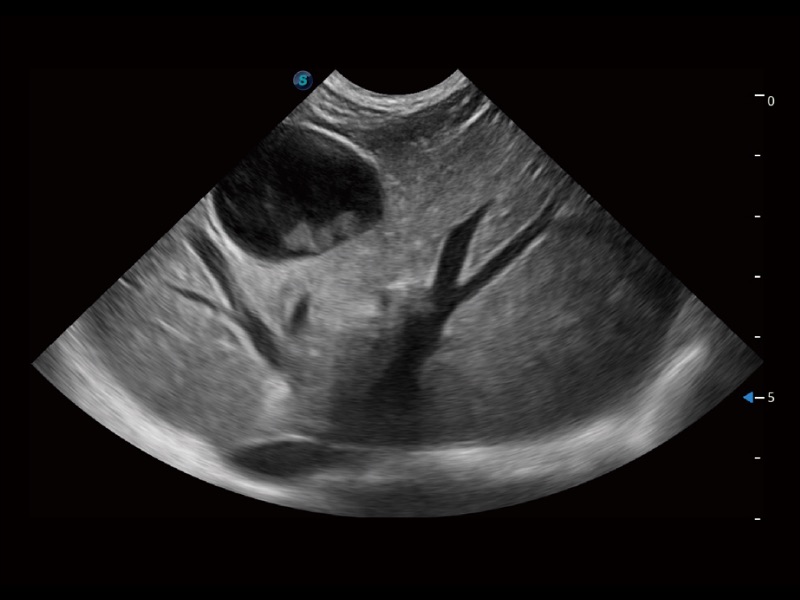

通过创新的 Matrix E自适应滤波器和超长时间域算法,极大提升超低速微细血流的检出能力,同时更精准地滤除软组织和噪声信号,为兽用医生提供以往无法通过常规血流获得的疾病诊断信息。

通过色彩血流和实时宽景相结合,可观察到完整的静脉或动脉的血流,方便医生检查。实时扫查过程中,如有任何操作失误也可以很容易地进行回扫擦除,而不会中断扫查。